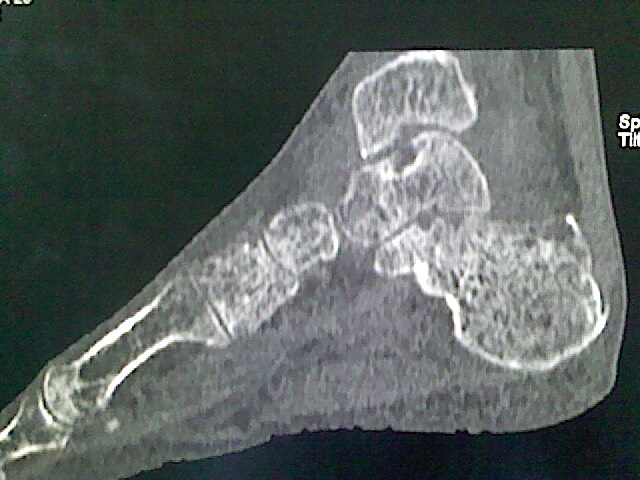

男,76岁,左小腿疼痛,不能站立

本例骨质改变主要表现为滑膜或韧带区的骨侵蚀融解(胫腓联合区骨质破坏无硬化边),距骨后部骨质破坏区有硬化边及死骨样改变.所以,本例考虑关节结核可能性大,绒毛膜结节性滑膜炎多发于中年,且极少见于膝髋以外的关节,骨质硬坏也以压陷吸收为主,有明显的硬化边,骨膜增生呈结节状(可以mr鉴别),所以本例暂除外.

另不除外可引起相似表现的其他炎症如布氏杆菌性关节炎等